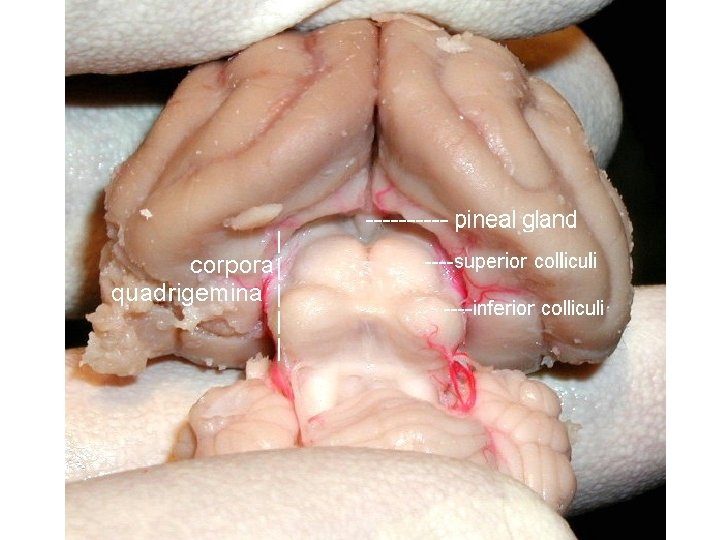

Šišinka Glandula pinealis; Corpus pineale „Epiphysis; Nadvěsek mozkový“ • vývojový vztah k parietálnímu oku • hatérie novozélandská (Sphenodon punctatus) • reakce na polarizované světlo (měsíční biorytmy)

Šišinka • za horním zadním koncem III. komory • součást epitalamu • rudimentární endokrinní žláza s tlumivým účinkem na činnost pohlavních žláz pubertas praecox • dorzálně vybíhá nad mozkový kmen (nad čtverohrbolí středního mozku) • melatonin změna hladiny během dne • acervulus cerebri (= vápenaté konkrementy u dospělých) – CT, MRI